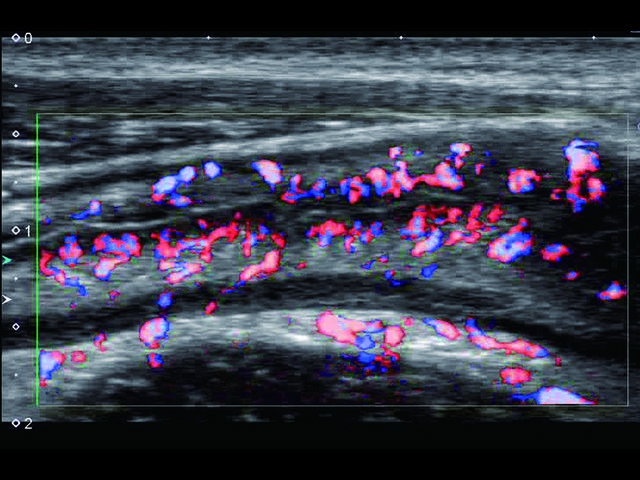

Обновленная версия легендарного УЗ-сканера. Стационарный аппарат экспертного класса Aplio 500 Toshiba NEW, визуализирует анатомические структуры в высоком разрешении. Модель позволяет выявить микрокальцификаты, новообразования, нарушения в работе сердца, сосудов и мышц. Присутствует функция виртуальной эндоскопии, 4D-сканирования, эластометрии тканей, УЗИ с контрастированием. За повышение качества изображения отвечают технологии ApliPure и Superb Microvascular Imaging. Первая задействует возможности пространственного и частотного кодирования, формирует цельный визуальный ряд с сохранением клинических маркеров. Вторая улучшает отображение микрососудистого русла, используя доплеровский эффект. Модель оснащена 21-дюймовым монитором, имеет 4 активных порта. Возможно подключение педиатрических, интраоперационных, лапароскопических и чреспищеводных датчиков.

- SMI. Опция, упрощающая визуализацию микроциркуляторного русла. С ее помощью обследуются сосуды с низкой интенсивностью кровотока, изучаются наиболее тонкие структуры. SMI упрощает диагностику новообразований, минимизирует вероятность ошибки.